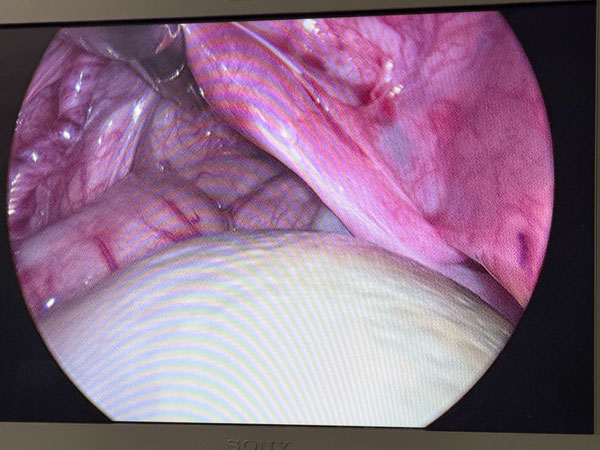

We proceeded with a Diagnostic Laparoscopy, which revealed a surprising anatomical finding. The mass was actually the left ovary, which had transformed into a large cyst and underwent torsion on its pedicle. Due to its size and the inherent mobility of the neonatal adnexa, it had migrated across the midline to the right lumbar region.

A Laparoscopic Ovarian Cystectomy was performed. Despite the torsion, we prioritized the preservation of ovarian tissue

Neonatal Ovarian Cysts are often the result of stimulation by maternal hormones and fetal gonadotropins. While many resolve spontaneously, cysts larger than 4-5 cm carry a significant risk of Torsion. Neonatal ovarian torsion can occur in utero or postnatally. Because the neonatal adnexa is highly mobile, a twisted, heavy cyst can "wander" throughout the abdomen, often leading to misleading preoperative imaging. Laparoscopy remains the gold standard for both definitive diagnosis and organ-sparing treatment.